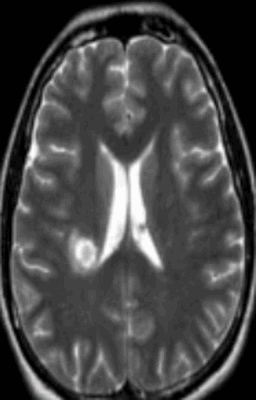

Гиперинтенсивные очаги

Выявление гиперинтенсивных, т.е. ярко выделяющихся на МР-сканах, очагов заставляет специалиста подозревать опухоль головного мозга, в том числе метастатического происхождения, гематому (в определенный момент от начала кровоизлияния), ишемию, отек, патологии сосудов (каверномы, артерио-венозные мальформации и пр.), абсцессы, обменные нарушения и т.п.

Очаги ишемии

Нарушения мозгового кровообращения приводят к кислородному голоданию тканей, что может спровоцировать их некроз (инфаркт). Ишемические очаги при Т2 взвешенных последовательностях выглядят как зоны с умеренно гиперинтенсивным сигналом неправильной формы. На более поздних сроках при проведении в Т2 ВИ или FLAIR режиме МРТ единичный очаг приобретает вид светлого пятна, что указывает на усугубление деструктивных процессов.